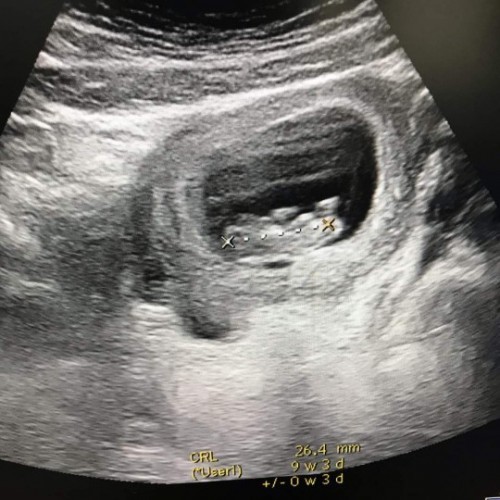

ท้อง9วีคหมอนัดซาวดูอายุครรภ์เจอตัวเด็กแต่ไม่เจอหัวใจเด็ก...จะเจอหัวใจเด็กช้าสุดกี่วีคคะแร้วถ้าเดกไม่มีหัวใจเดกจะหยุดการเจริญเติบโตมั๊ยคะ..#ไม่มีอาการผิดปกติ #คุณหมอจะหั้ยเอาออกอย่างเดียวเรย😭😭

9วีคไม่เจอหัวใจแสดงว่าน้องไม่อยู่แล้วจ้าแม่ คุณหมอจึงต้องยุติการตั้งครรภ์เพื่อความปลอดภัยต่อตัวคุณแม่จ้า

เราเจอตอน6วีคค่ะ ถ้าไม่เจอหัวใจน้องเต้นน้องจึงไม่มีชีวิตค่ะมีแค่ตัว คุณหมอก็จะยุติการตั้งครรภ์ค่ะ